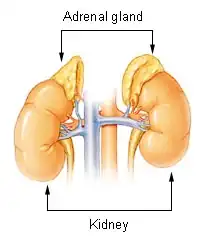

The pituitary gland consists of two parts, the anterior (front) and posterior (back) pituitary. Both parts release hormones that control numerous other organs. In pituitary apoplexy, the main initial problem is a lack of secretion of adrenocorticotropic hormone (ACTH, corticotropin), which stimulates the secretion of cortisol by the adrenal gland. This occurs in 70% of those with pituitary apoplexy. A sudden lack of cortisol in the body leads to a constellation of symptoms called "adrenal crisis" or "Addisonian crisis" (after a complication of Addison's disease, the main cause of adrenal dysfunction and low cortisol levels).[1] The main problems are low blood pressure (particularly on standing), low blood sugars (which can lead to coma) and abdominal pain; the low blood pressure can be life-threatening and requires immediate medical attention.[6]